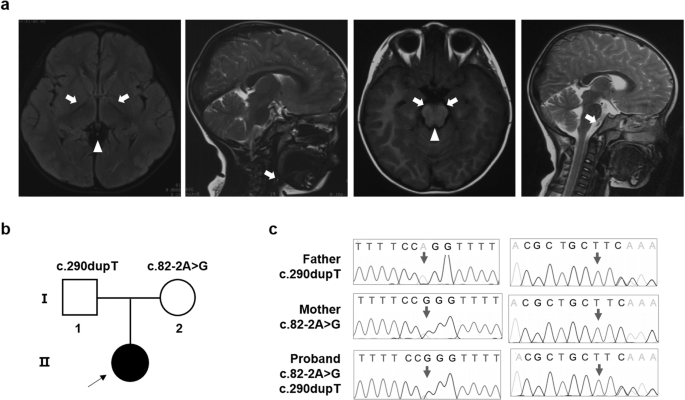

The individual (II-1) was born into nonconsanguineous healthy Chinese family with a normal gestational and delivery records. She fell the development milestone, with unsteady gait at the age of 15 months, and received rehabilitation training for two months, however, no improvement in her symptoms. By age 2, she developed uninterrupted strabismus in her left eye and still showed gait disturbance. When she was three years old, the candidate walked with drunken gait, along with weak muscular strength, reduced muscle tension, malnutrition but well developed reflexes and mental response. The face of patient was yellow, with yellow palms and feet, and the back of the neck was ciliated. Magnetic resonance imaging (MRI) in the cerebral peduncles corticospinal tract demonstrated patchy, spot-like, long T1 and T2 signal shadows symmetrically and fluid attenuated inversion recovery (FLAIR) showed equal signal. MRI in the cerebral bridge appeared flakes T2 weighted image (T2WI), hypo-intense T2WI FLAIR signal and spot-like hypo-intense apparent diffusion coefficient (ADC) signal (Fig. 1a). Electromyogram/evoked potentials test (EMG/EP) revealed that sensory nerve conduction slows in the left gastrocnemius muscle (35.3 m/s, normal range 40–60 m/s) and motor nerve conduction was normal. No further sensory testing was done due to the child was unable to cooperate. Metabolic investigation showed increased blood lactate (3.14, normal range 0.50–2.20 mM) and β- hydroxybutyric acid (1.18, normal range 0.02–0.27 mM). Amino acid and acylcarnitine profile analysis were normal. Other tests showed increased aspartate amino acid transferase (42.2, normal range 0.0–35.0 U/L), lactate dehydrogenase (247.3, normal range 109.0–245 U/L) and α-hydrobutyrate dehydrogenase (260.8, normal range 90.0–250.0 U/L), indicating an impaired liver function. The symptom was partly overlap with LS (progressive neurological impaired with motor developmental delay and raised blood lactate level). However, the neurological abnormal signs was focus on cerebral peduncles corticospinal and cerebral bridge, thus this patient was diagnosis with LLS.

Segregation analysis, sanger sequence and MRI manifestation. a MRI image of proband. The arrow indicated the patchy, spot-like, long T1 and T2 signal shadows symmetrically in cerebral peduncles corticospinal tract. The triangle indicated the flakes T2WI in the cerebral bridge. b Segregation analysis of affected individual. Rectangles indicate males, circles female, and solid circle represents affected individual. The proband was pointed out by arrow. c Sanger sequence of the affected family. The arrows indicate mutation sites

Next-generation sequencing was performed to detect the disease-causing gene of the probing, after the filtering with established criteria [27], a novel splice site variant (c.82-2 A > G, intron 1) and a novel insertion variant (c.290dupT, exon 3) in TMEM126B (NM_018480.7) were identified and no clinically significant mitochondrial genomic-related variants were detected. Segregation analysis confirmed that c.82-2 A > G was maternal inherited while c.290dupT was paternal (Fig. 1b, c).